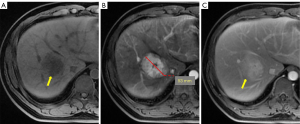

An enhanced and prolonged MRI examination of the liver was performed to confirm a diagnosis. MRI demonstrated a well-demarcated mass sized 53 mm × 45 mm × 41 mm in the right liver lobe that showed homogeneous hypointensity on T1WI (Figure 2A), hyperintensity on T2WI and DWI, and early significant enhancement (Figure 2B). A central scar in the lesion with a 2-minute delayed enhancement mimicked the manifestation of focal nodular hyperplasia (FNH) (Figure 2C). There were no obvious abnormalities in the remaining liver. All figures and tables in the article are original.

AH represents a diagnostic dilemma because it has no specific characteristics on CT and MRI images and has overlapping features with angiosarcoma (9). Liver AH is a rare but distinct subtype of hemangioma (10). Only 5 relevant articles have reported cases of liver AH (Table 1). A recent study on liver AH showed that its growth is noninvasive in situ and requires aggressive resection considering its large mass effect (11). Here, we reported a rare case of a growing AH that mimicked FNH in the liver. Regretfully, we examined gadolinium-enhanced MR imaging, and the MR imaging with the hepatobiliary agent was ignored. FNH was iso- or hyperintense on delayed imaging, which helped to improve the specificity for characterization and diagnosis (12). We observed the characteristic central scar in the lesion, which was not distinct in T1WI or T2WI. The lesion presented as hyperintense in T2WI and hypointense in T1WI and showed no enhancement in arterial (Figure 2B) or portal phase but did show delayed enhancement after a 2-minute delay (Figure 2C). The typical appearance of the central scar was hypointense on T1WI and hyperintense on T2WI. In one study, hyperintense central scar was demonstrated to be present in 69.1% of cases and in 78% of cases with marked moderate hypointensity on T1WI images (13). Considering the important role of Gd-enhanced T1WI sequences, this case was misdiagnosed as FNH. The MRI demonstrated a lack of aggressive features. When a lesion is diagnosed as benign, the management is primarily surveillance (14). Overwhelming evidence suggests that AH exhibits benign biologic behavior (15). Furthermore, the management and surveillance of AH remain challenging (16). A better understanding of the growth conditions will help guide decisions concerning the optimal treatment of AH (17). Thus, our case report may help settle the controversy concerning whether management should be a surveillance-first or surgery-first approach.